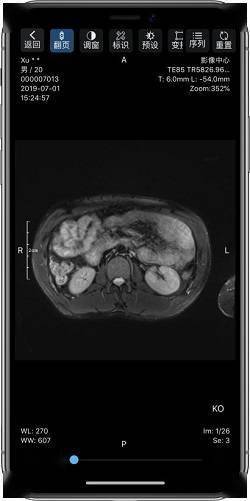

(患者可扫描报告单上的二维码获取所有检查数据)